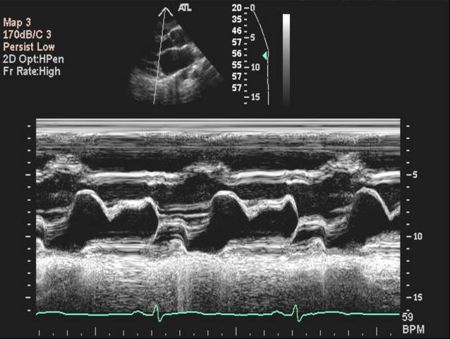

M mode echocardiography

Mitral Valve M-mode Analysis

- Anterior leaflet with E/A appearance of diastology

- Decreased EF slope in MS

- Scalloping of leaflet tip in end systole in prolapse